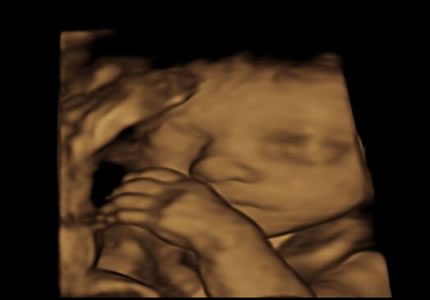

4D Bonding Experiences (24 – 34 Weeks)

Enjoy a magical glimpse of your baby’s face in real time. Ideal during 26–30 weeks when fluid and positioning are optimal.

- Utilising our advanced imaging technology, we offer you a magical window into your baby’s world. You can watch your baby’s real-time expressions, such as yawning or smiling. This session is best booked between 26–30 weeks when the baby has developed enough features for clear, detailed viewing.